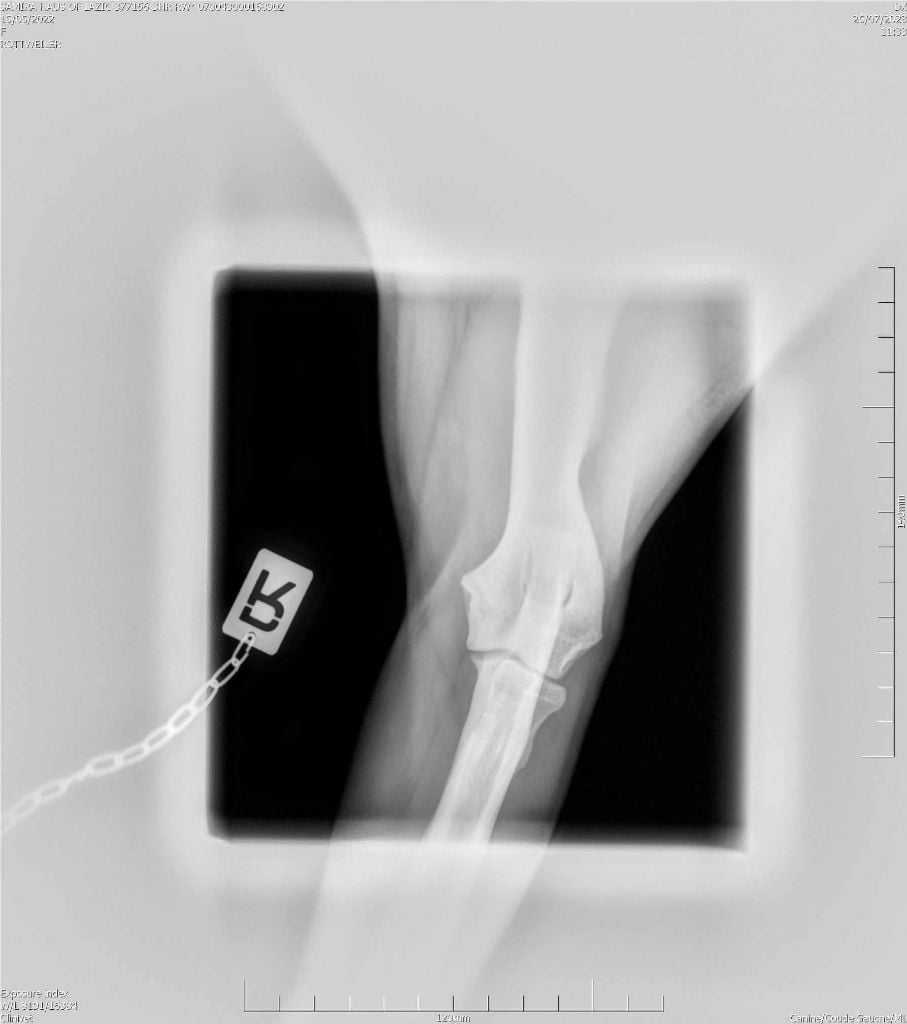

RADIO COUDE OFFICIELLE

COUDE SUITE

ADN : FAIT DYSPLASIE COUDES : ED0 DYSPLASIE HANCHES : HDA JLPP : CLEAR |